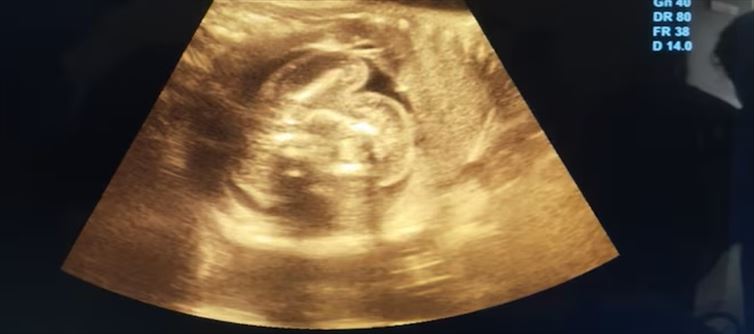

In Buldhana, Maharashtra, a very uncommon medical occurrence occurred when a baby was found within the womb of an unborn kid. Two days ago, when a 32-year-old lady had a sonography, a case of "foetus-in-fetu" was discovered at a government hospital. just 200 examples of this uncommon congenital defect have been reported globally, with just 15 to 20 of those occurrences occurring in India.

Gynecologist Dr. prasad Agarwal, who found the non-developing fetus, stated, "I was initially surprised and then carefully re-examined the images." He went on to say, "It was a case of a foetus-in-fetu."

Although the precise source of this illness is unknown, it is thought to be caused by an aberration that occurred during the development of identical twins. Since the parasitic twin cannot survive on its own, it is regarded as a developmental aberration rather than a legitimate twin pregnancy.